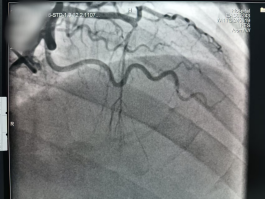

冠脉造影            支架植入术后

14:05,患者直接从急诊科转入导管室;14:10,穿刺成功并置入血管鞘;14:13,冠脉造影显示左冠脉前降支中段急性闭塞;14:20,导丝通过闭塞病变,血管恢复血流,患者胸闷症状显著缓解。后续,医疗团队顺利完成球囊扩张及支架植入,14:40 手术结束,患者安全转入心内科监护病房。从入院到血管开通,全程仅 35 分钟,远低于胸痛中心平均救治时间。